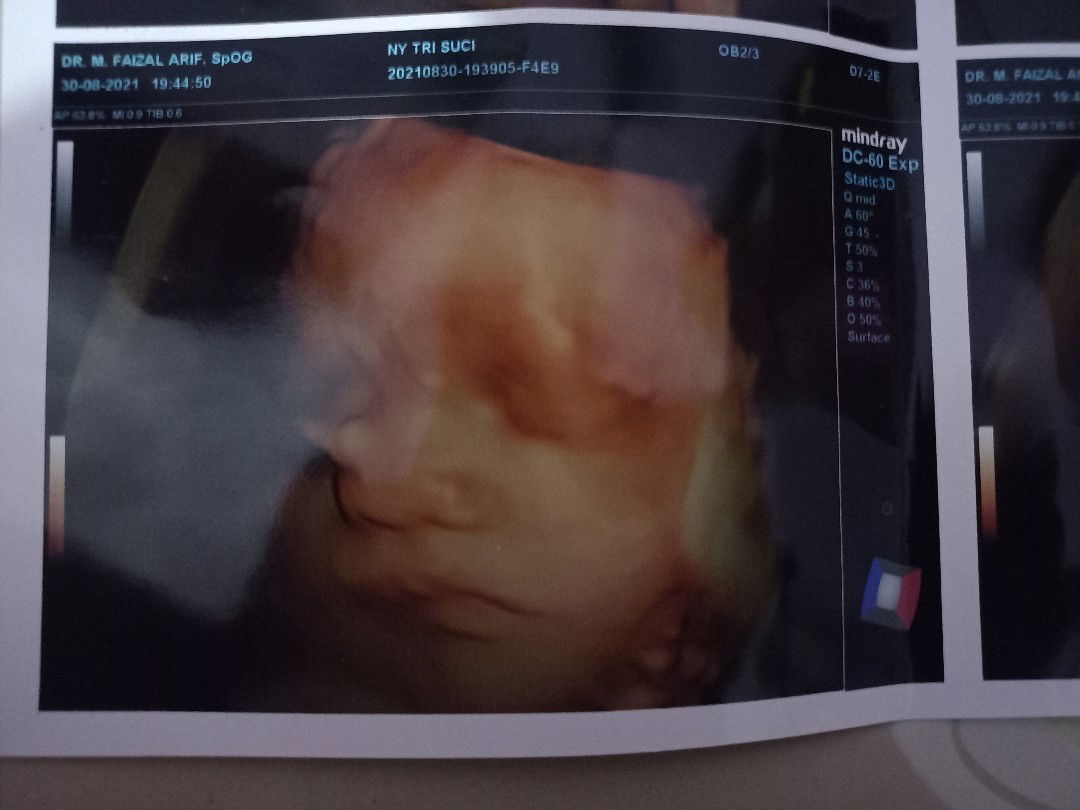

Ini saya barusan USG juga bund 6 week